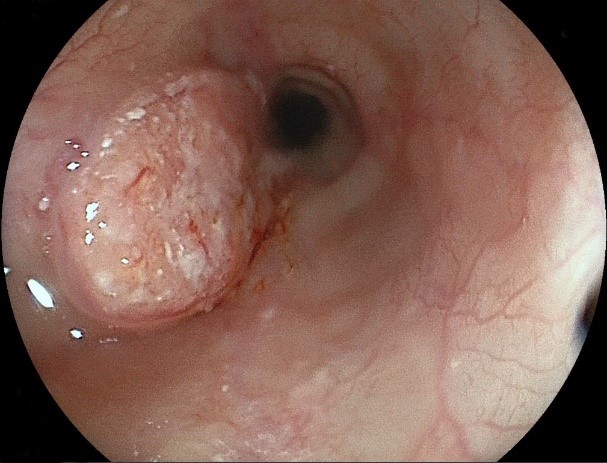

進行食道癌(隆起型)の例

進行食道癌(1型:隆起型)では、画面左側に丈の高い隆起性病変を認めます。

このような病変は外科的手術が必要となります。